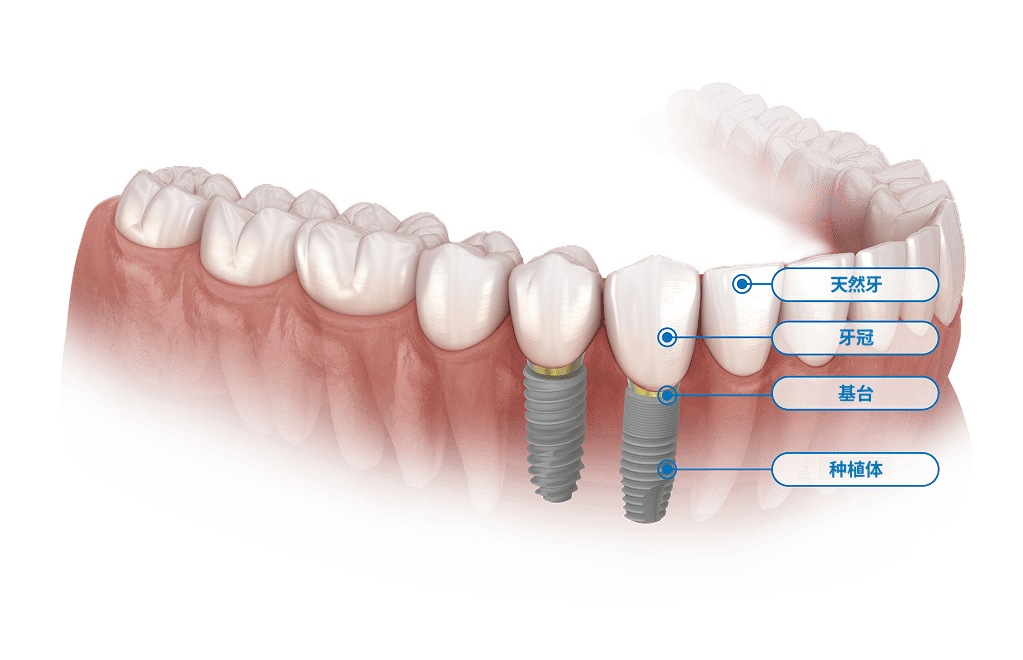

什么是

种植牙?

种植牙是目前最接近健康天然牙齿的修复方式。